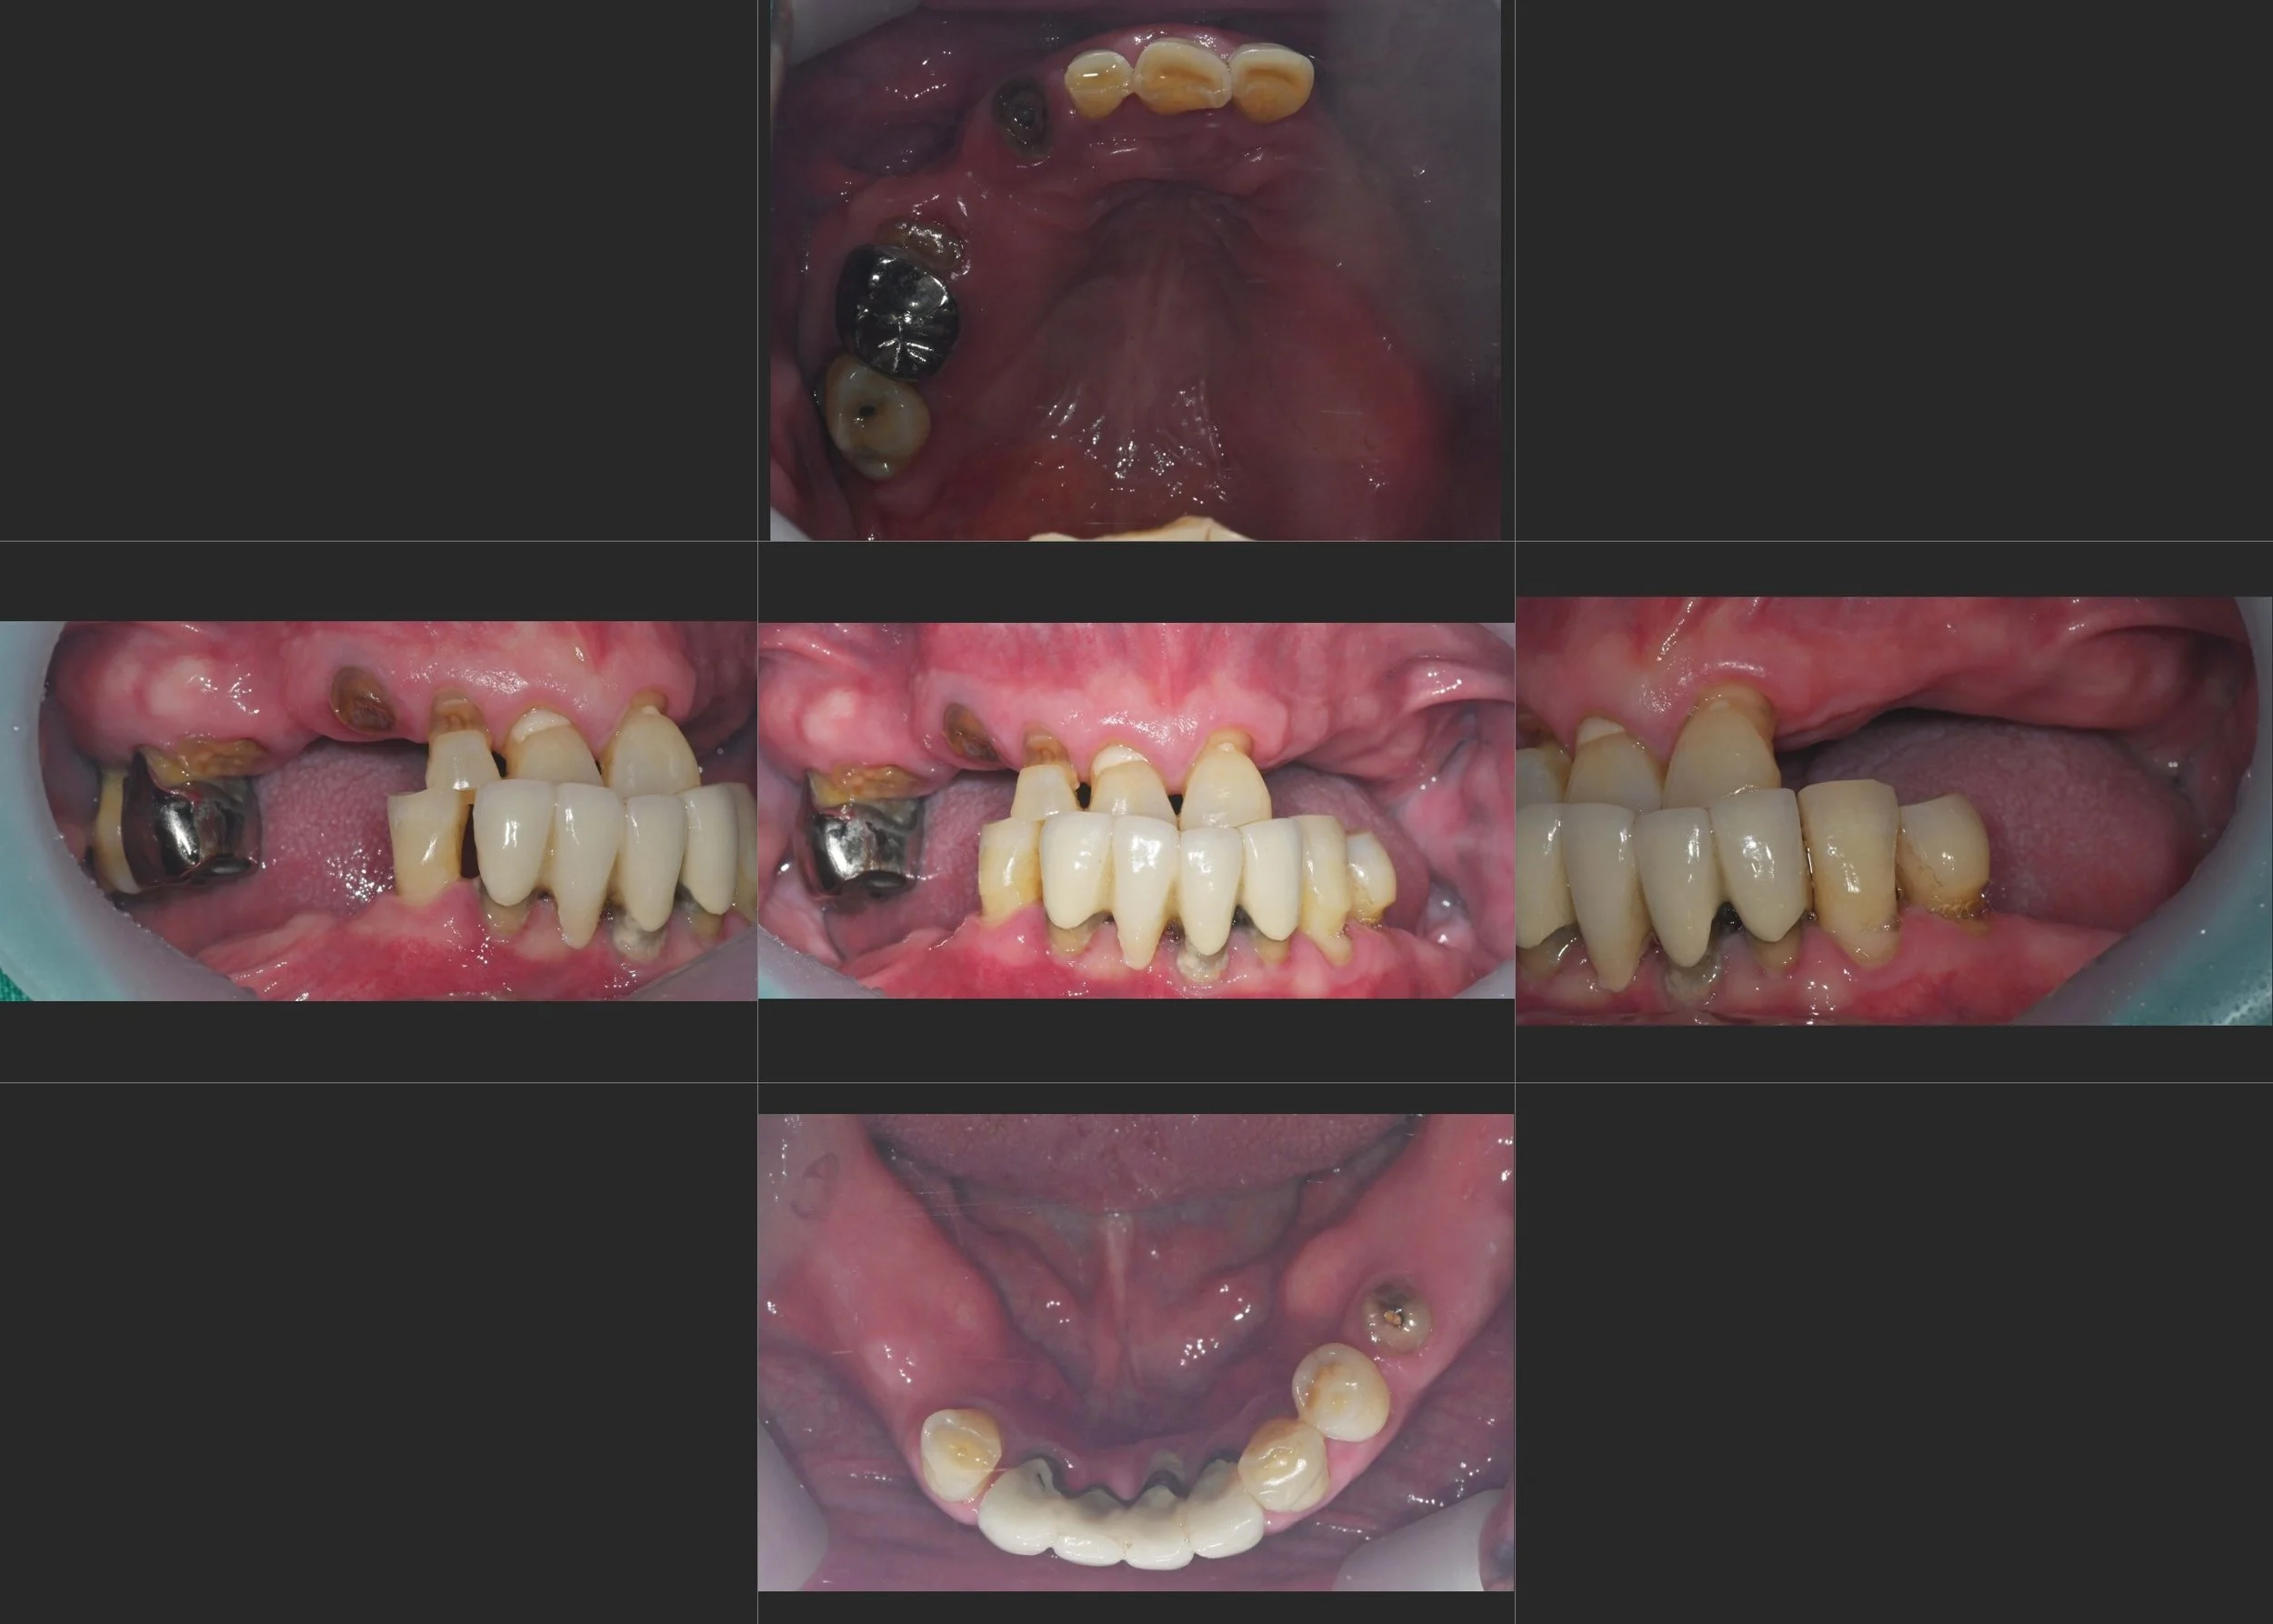

INTRA ORAL - AFTER

A prosthetic-driven rehabilitation strategy was adopted.

Posterior maxillary implant placement was performed in conjunction with bone grafting to compensate for sinus-related bone deficiency.

Following vertical augmentation, the occlusal plane was repositioned horizontally to correct the functional Class III pattern.

Natural teeth with favourable prognosis were preserved,

and a controlled anterior overjet was established to guide a more harmonious occlusion and facial appearance.